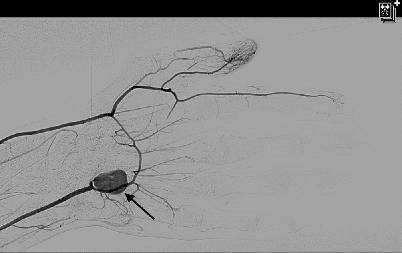

Die Diagnose eines Pseudoaneurysmas der A. ulnaris wurde in einer farbkodierten duplexsonographischen Ultraschalluntersuchung während des Ambulanzbesuchs gestellt. Das Farbdopplerbild zeigte das typische „Yin-Yang“ Zeichen (Abb. 2). Die Indikation zur Rekonstruktion wurde aufgrund der Ischämie und der Behinderung bei der Berufstätigkeit gestellt. Nach zwei Wochen erfolgte die Aufnahme und am selben Tag wurde eine Angiographie zur Operationsplanung durchgeführt, welche ein Pseudoaneurysma der A. ulnaris mit Verschluss des oberflächlichen Handbogens zeigte (Abb. 3).

Abb. 2

Farbdopplerbild zeigt das typische „Yin-Yang“ Zeichen (Pfeil) im Pseudoaneurysma der A. ulnaris

Abb. 3

Präoperative Angiographie zur Operationsplanung: Pseudoaneurysma der A. ulnaris (Pfeil) und Verschluss des Arcus palmaris superficialis